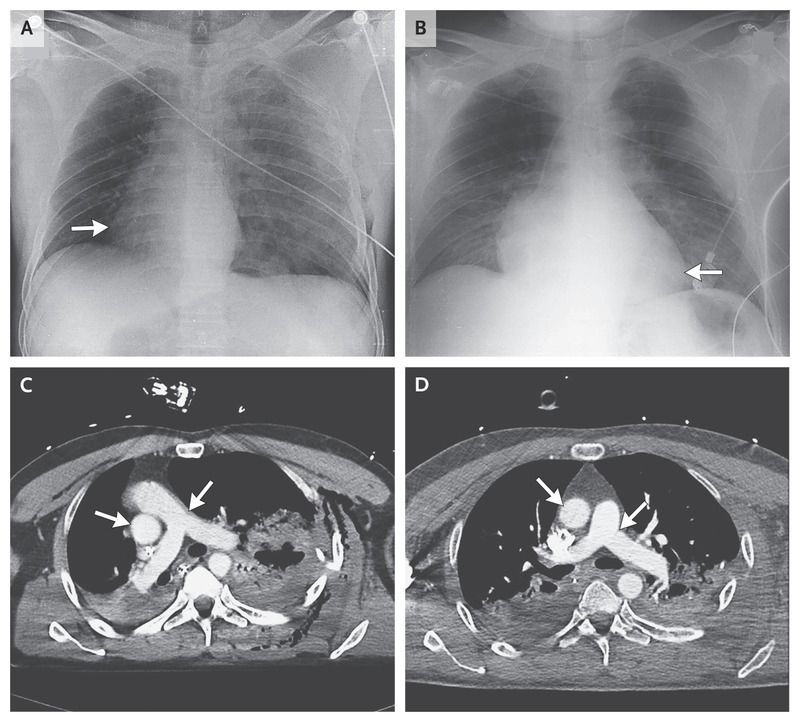

A chest radiograph and computed tomographic (CT) scan showed a 90-degree rightward rotation of the cardiac silhouette (Fig 1, Panel A, arrow) and great vessels (Fig 1, Panel C, arrows), with left tension pneumothorax and multiple rib fractures (Fig 2, Picture 1), bilateral pulmonary contusion (Fig 2, Pictures 1 and 3), and ruptured spleen.

A total of 24 hours after pleural drainage, the patient’s heart moved leftward, back into its original position (Fig 1, Panel B, arrow), with complete anatomical and physiological recovery of the great vessels (Fig 1, Panel D, arrows) and other areas (Fig 2, Pictures 2, 4, and 6).